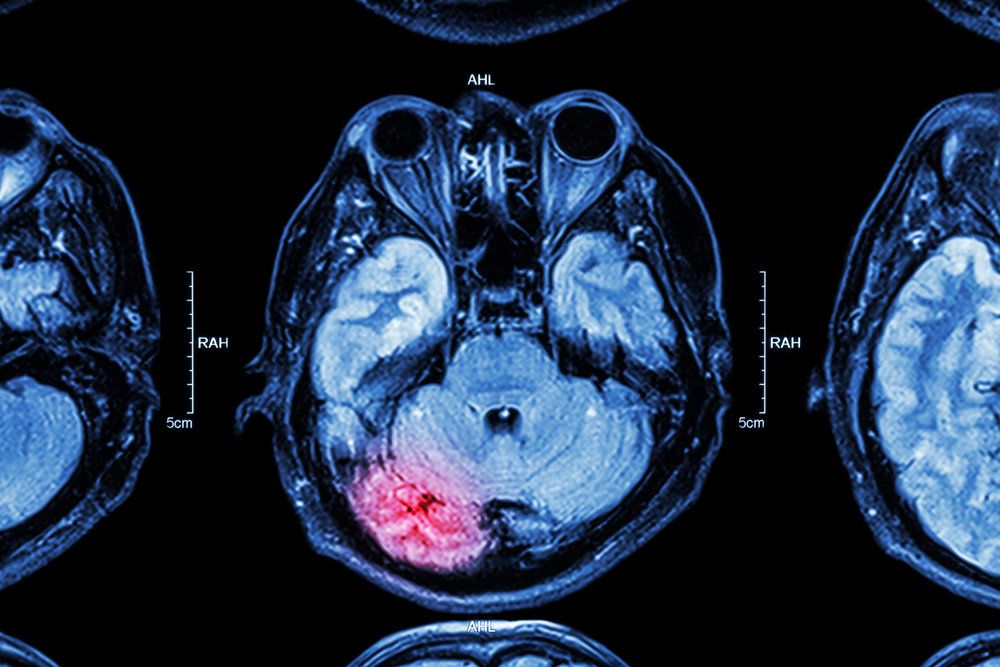

TBIs can range from mild to severe. A TBI is mild if loss of consciousness or confusion and disorientation last for less than 30 minutes. A concussion, for example, is considered a mild TBI. Magnetic resonance imaging (MRI) and computed tomography (CT) scans are often conducted in the case of a mild TBI, and the injured person may suffer adverse effects for a year or longer.